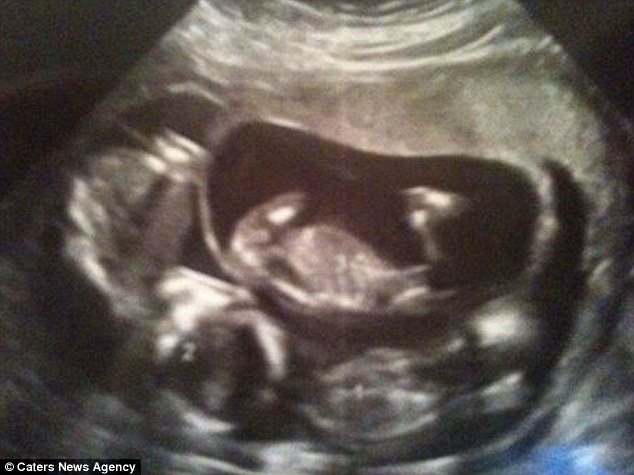

Кога парот го направил првиот ултразвук шокот бил уште поголем, на мониторот се виделе 3 бебиња. Сестрите се погледнале со насмевка и на нивното лице се гледало неверување. Кристи вели:

Ми рекоа да погледнам на мониторот и јас можев да видам дека имаше 3 бебиња. Само реков, Ох Господе и не можев да верувам - мислев дека е сон.